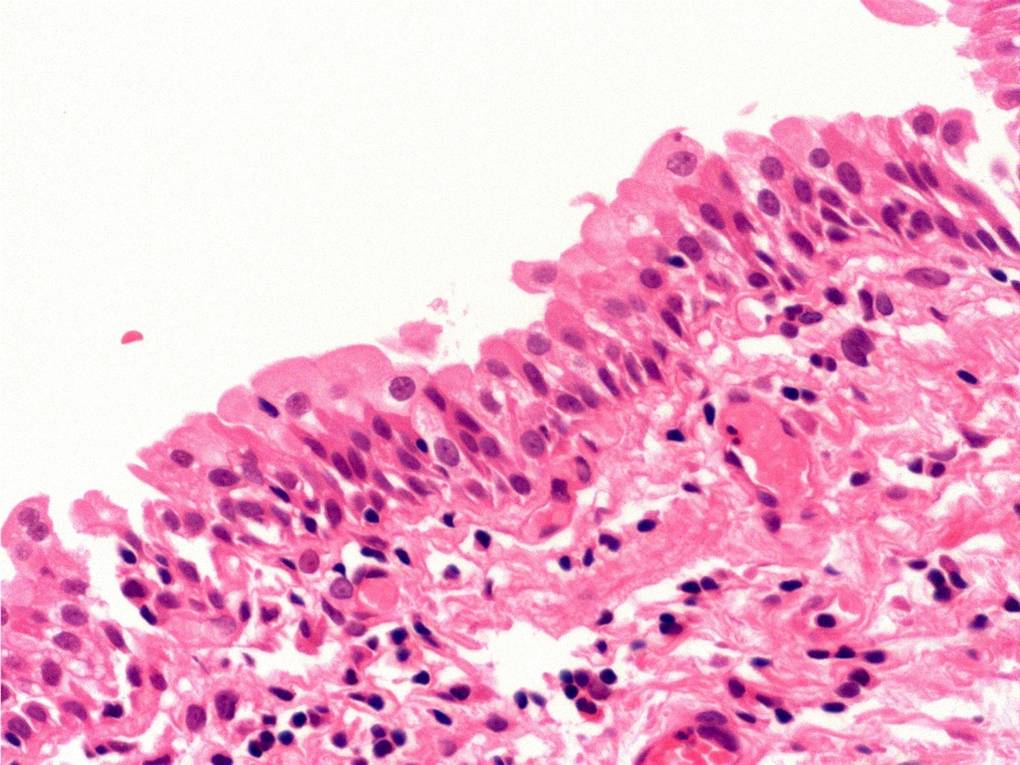

Bladder Flat Lesions

Case ID: 80